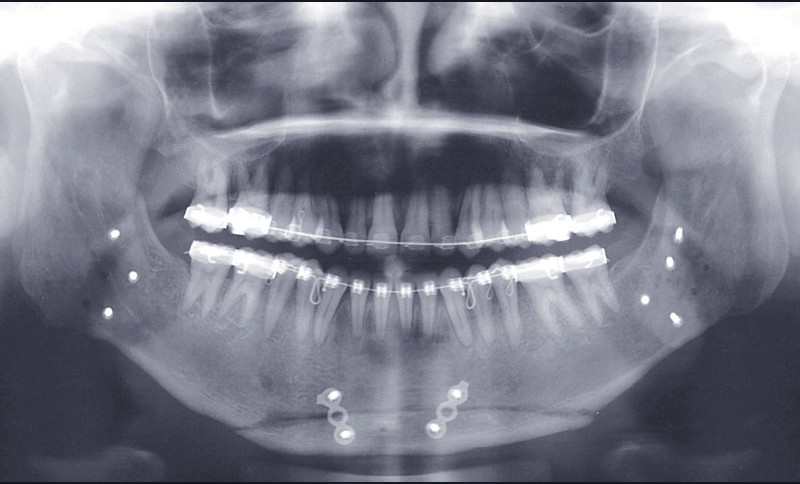

Distalisation molaire mandibulaire par corticotomies associées aux miniplaques (fig. 7)

Le recul molaire a apporté l’espace nécessaire à la correction de l’encombrement avec en plus un léger recul incisif qui a permis de positionner de façon idéale l’incisive dans la symphyse. Une distalisation des secteurs latéraux de 3 mm à droite et 2 mm à gauche permettant aussi de symétriser les relations molaires a donc été obtenue en…